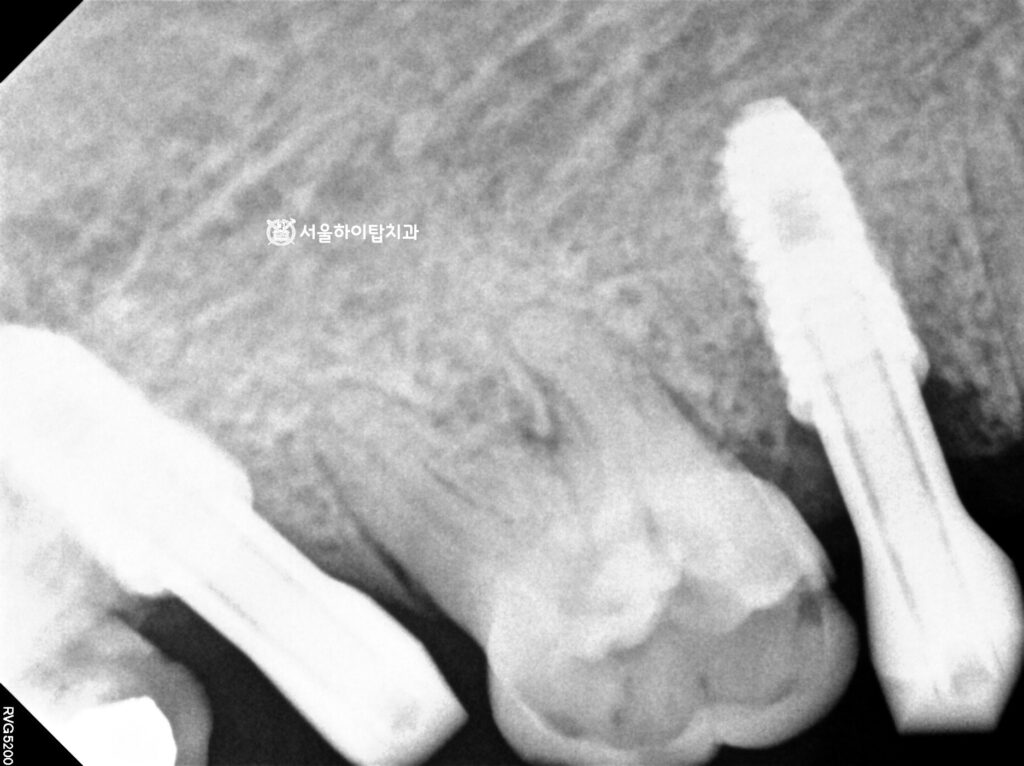

위턱도 동일한 방식으로 진행되지만,

기울어진 사랑니 때문에 공간이 다소 부족한 상태입니다.

부평 치과 에서는 두 개의 어금니 자리에 각각 식립하는 것이 이상적이라 말씀드리지만,

공간 제약으로 인해 1개만 식립하고, 추후 크라운을 크게 만들어주면

빈 공간을 최소화하고 저작과 심미를 동시에 회복할 수 있습니다.

수술 완료

정밀한 CT를 통해 나온 데이터에 따라 정확한 위치에 심긴 모습입니다.